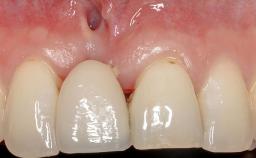

A 30-year-old woman was referred by her general dentist for evaluation of an esthetic complication related to previous implant treatment for congenitally missing maxillary lateral incisors. The patient’s chief complaint was the inadequate esthetic appearance of her smile. The case demonstrates the use of a combined approach to achieve optimal results. Two different flap designs - a tunnel technique and a coronally advanced flap - are employed based on the surgical objectives for the affected site.

Soft Tissue Grafting Yes

Soft Tissue Contour and Volume Slightly compromised